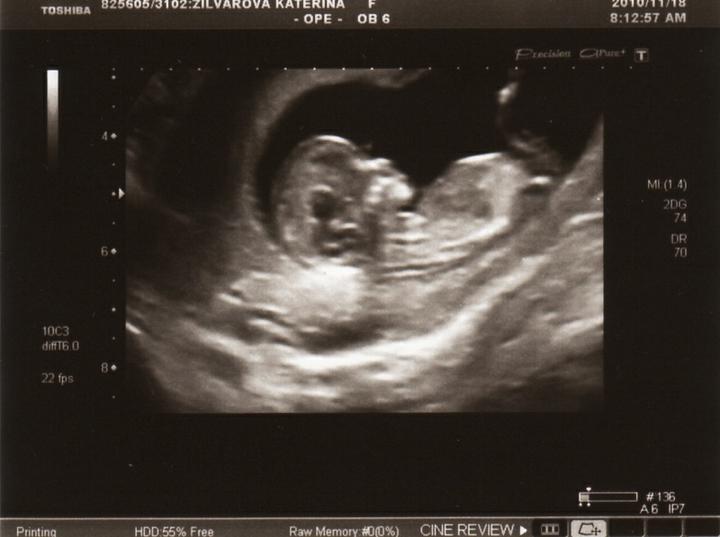

NT 1,4mm, tedy negativní, miminko měří 5cm, termín porodu 4.6.

5.11. odběr krve, 18.11. screening

krev ze 7tt HCG přes 35.000 :o)))) UTZ objednán na 18.11.